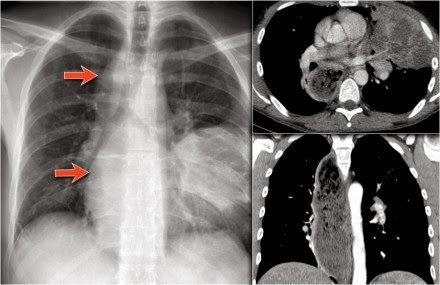

Here an example

of a large lesion in the right lower lobe, which is difficult to detect on the PA-film, unless when you give special attention to the hidden areas.

Here a pneumonia which was hidden in the right lower lobe mainly below the level of the dome of the diaphragm (red arrow).

Notice the increase in density on the lateral film in the lower vertebral region.

You may have to enlarge the image to get a better view.